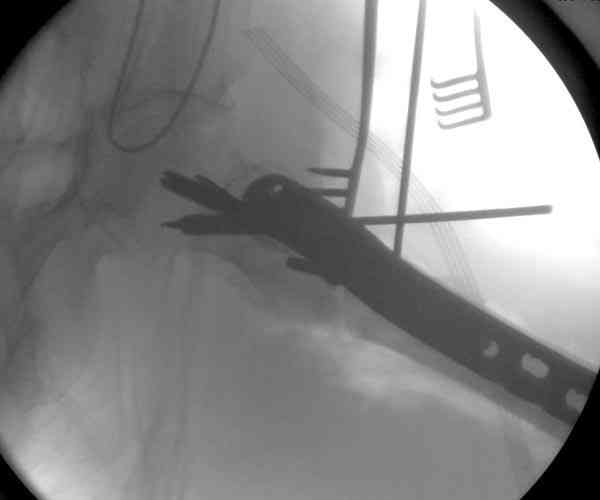

23.08.07г. на форуме был представлен больной 68 лет с диагнозом: несросшийся подвертельный косой перелом. http://www.weborto.net/forum/1187804790/ Больной после неудачной операции в одном районе в течении 7 месяцев был прикован к постели, с пролежнями в обл. крестца. Больной в течении 10 дней подготовлен к операции, НВ-153, эритр.-4,5, соэ-7, ВСК-3-3,40. ПТИ-81.ФНГ-3100. Мочевина, билирубин, АЛТ,АСТ в пределах нормы. Для остеосинтеза готовили пластину клинковую, штопор Сиваша . Во время операции дистальный отломок легко мобилизовали, проксимальный отломок был ротирован и сильно приведен медиально( m. iliopsoas), а также сильно замурован плотной как хрящ рубцовой тканью. Линия излома косая около 10 см., наружная стенка большого вертеля почти не было. У малого вертеля отсекли сухожилие m. iliopsoas и дальше на глубине начали распатором мобилизовать конец проксимального отломка, который был сильно приведен и находился глубоко , когда начали отделять изогнутом распатором заднюю часть конца и чуть подтянут отломка и тут начался сильнейшая кровотечения, фонтаном, найти сосуд и остановить кровотечение в ране не удалось, сосуд вместо с рубцовой тканью ушел назад и медиально отломка. Срочно рану туго тампонировали и остановили кровотечение, вызвали сосудистого хирурга,но их не нашли, оказалась один в отпуске, двое на экстренном вызове в районах. Передным доступом (по L. vasorum ) обнажали бедренную артерию, провели резиновую держальку и временно сосуд зажали, открыли рану , убрали тампон, но на глубине в толще рубцовых тканей поврежденный сосуд найти не удаётся. Поэтому переднюю рану расширили вниз, при ревизии бедренная артерия не повреждена, а глубокая бедренная артерия повреждена пристеночно, примерно на 2-3см от место отхождения от бедренной артерии, не доходя до ответвлений на огибаюших артерий. А одноимённая вена повреждена на протяжении около 3х см, и в данный момент восстановить не удается и пришлось перевязать оба конца, на артерию наложили поперечный сосудистый шов, бедренную артерию освободили, кровоток восстановился. Но теперь начала вся рана кровить! Венозный застой! К этому времени состояние больного резко ухудшилось, наступил клинический смерть, с трудом реанимировали, вроде б и кровотечение остановилось, как а/д подняли до 100/60мм опять начался кровотечение, коагулятором остановить не удаётся, рану туго тампонировали, перелито больше одного литра эр. массы и плазмы,и ешё кровозаменители, стабизол, рефортан и др. а/д держим 90/60, интесивная терапия против ДВС синдрома. Реаниматологи не разрешают производить остеосинтез, так как гемодинамика нестабильная , держиться под вазопрессорами. Через час состояние больного не улучшается , реаниматологи дали 10 минут и мы быстро кое как репонировали, остеосинтез продолной пластиной ЦИТО, но шурупы в проксимальном отломке плохо держутся, (остеопороз ), но другого выхода не было, для клинковой пластини просто небыло времени. Тканевое и капиллярное кровотечение продолжается, рану туго тампонировали и наводяшие швы на рану. Наложили гипсовой сапожок с деротатором. Больной находился в общей реанимационной отд. 20 дней и вышел из критического состояния. Но на контр. Р-грамме шурупы как и предпологали не держались, имеется ротация проксимального отломка, хотя ось бедра правильная и клинически деформации нет, даже определяется клиническая схватка . Я долго думал, вынести это на форум или нет, позвонил Челнокову А Н, он сказал <надо быть честным до конца, доложил на форуме, надо сообшить и о резултатах> Уважаемые коллеги! Какие были допушены ошибки? И какие рекомендации будут теперь? . P. S. за некачественный р-снимок прошу прошения!